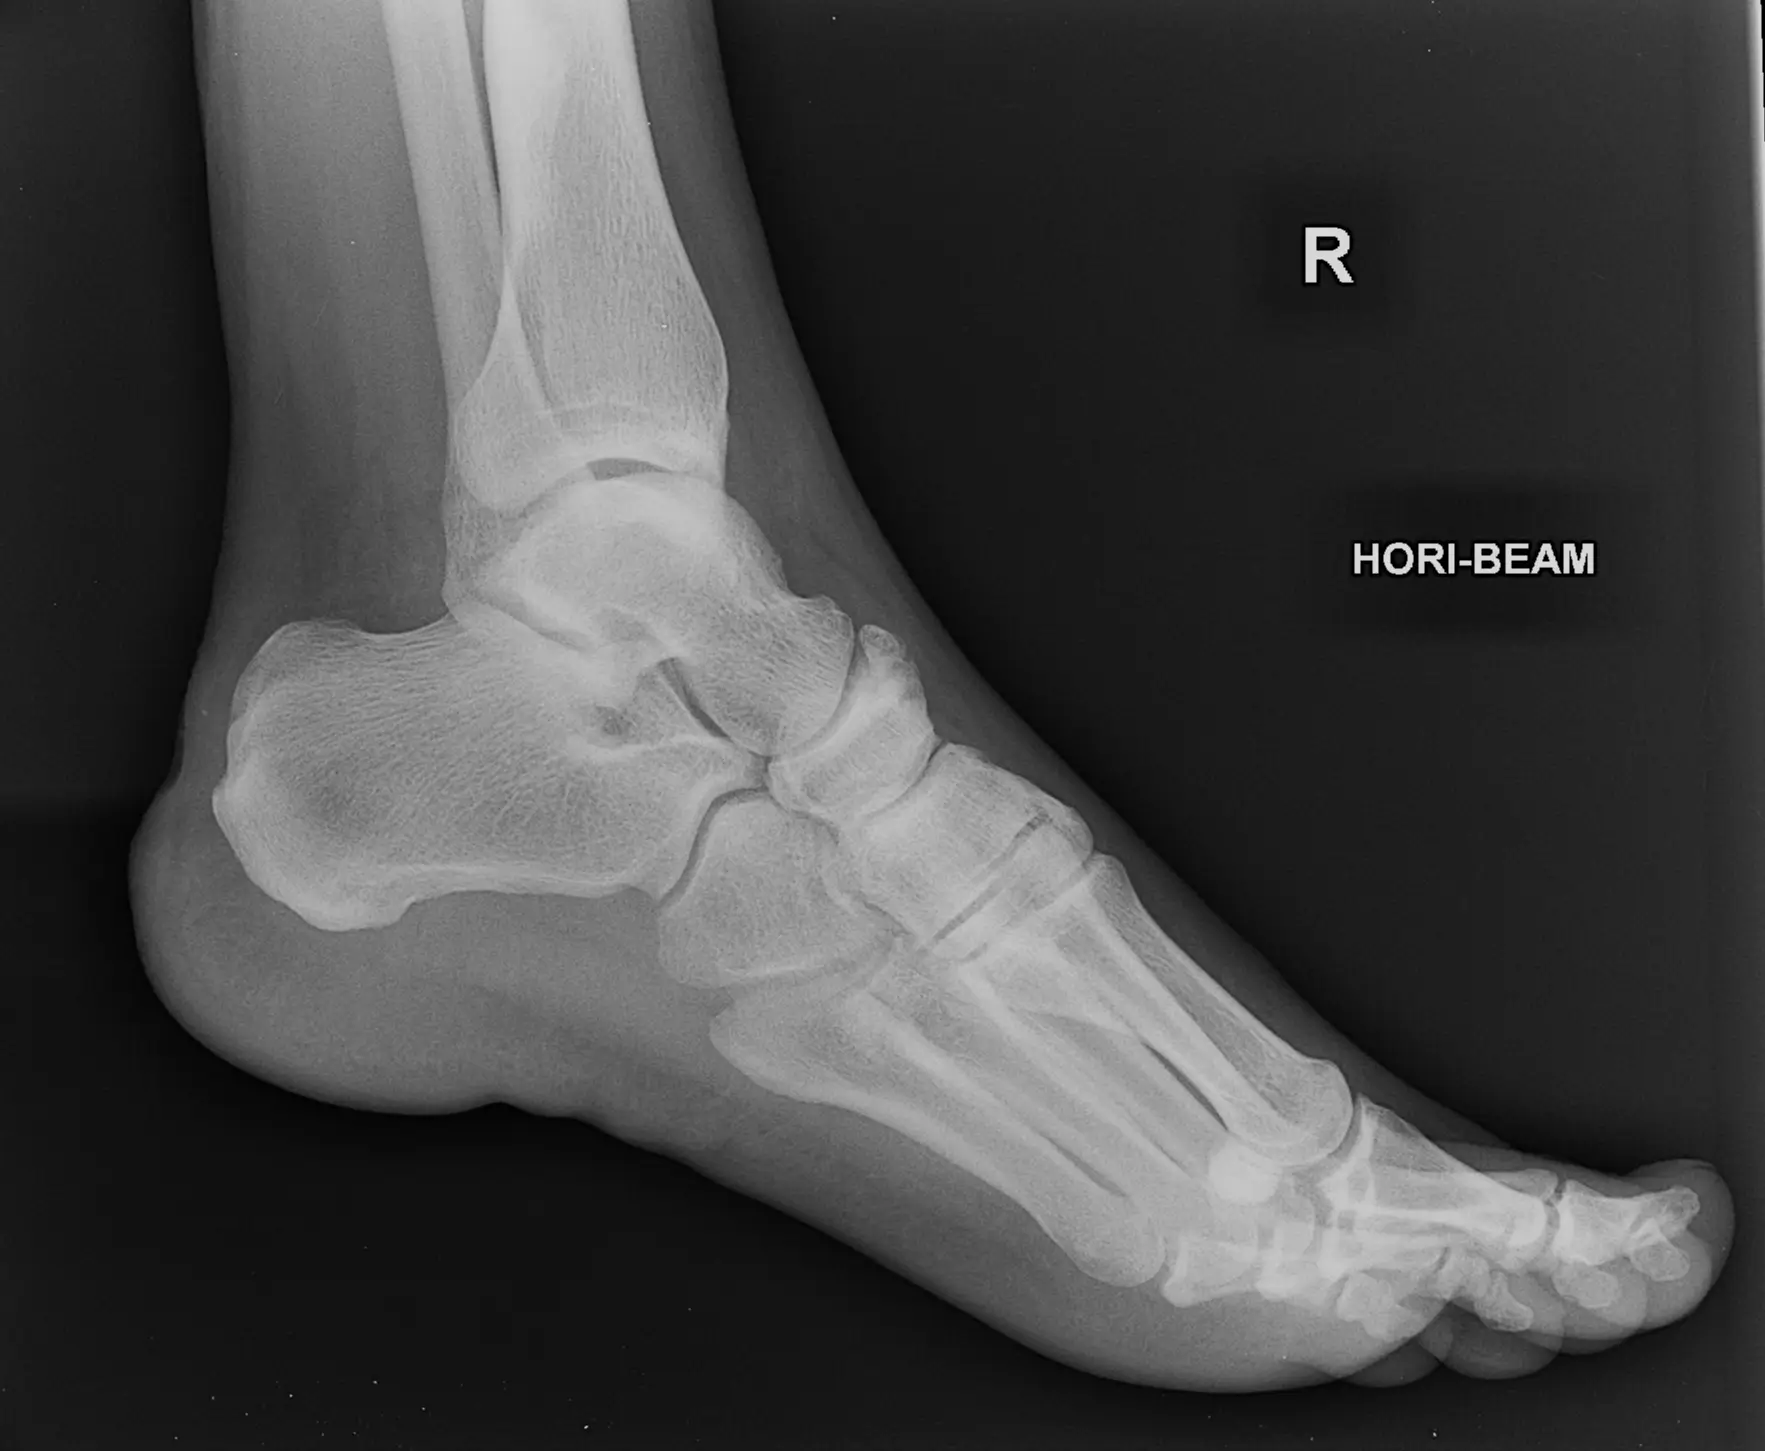

X-ray Left Heel Lateral/Axial

An X-ray of the calcaneum (the bone of the heel) allows for visualization of the calcaneum and the soft tissues (skin and muscles) that surround it.